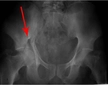

Pelvis yaralanmaları, hareket kabiliyetini önemli ölçüde etkileyebilir. Pelvisin stabilitesi bozulduğunda, yürüyüş ve diğer temel hareketler zorlaşabilir. Bu tür yaralanmalar, rehabilitasyon sürecini uzatabilir ve günlük yaşamda zorluklar yaratabilir. Kişisel bir deneyimim yok, ancak pelvis yaralanmalarının fiziksel terapideki etkilerini gözlemlemiş olan birçok kişi var.